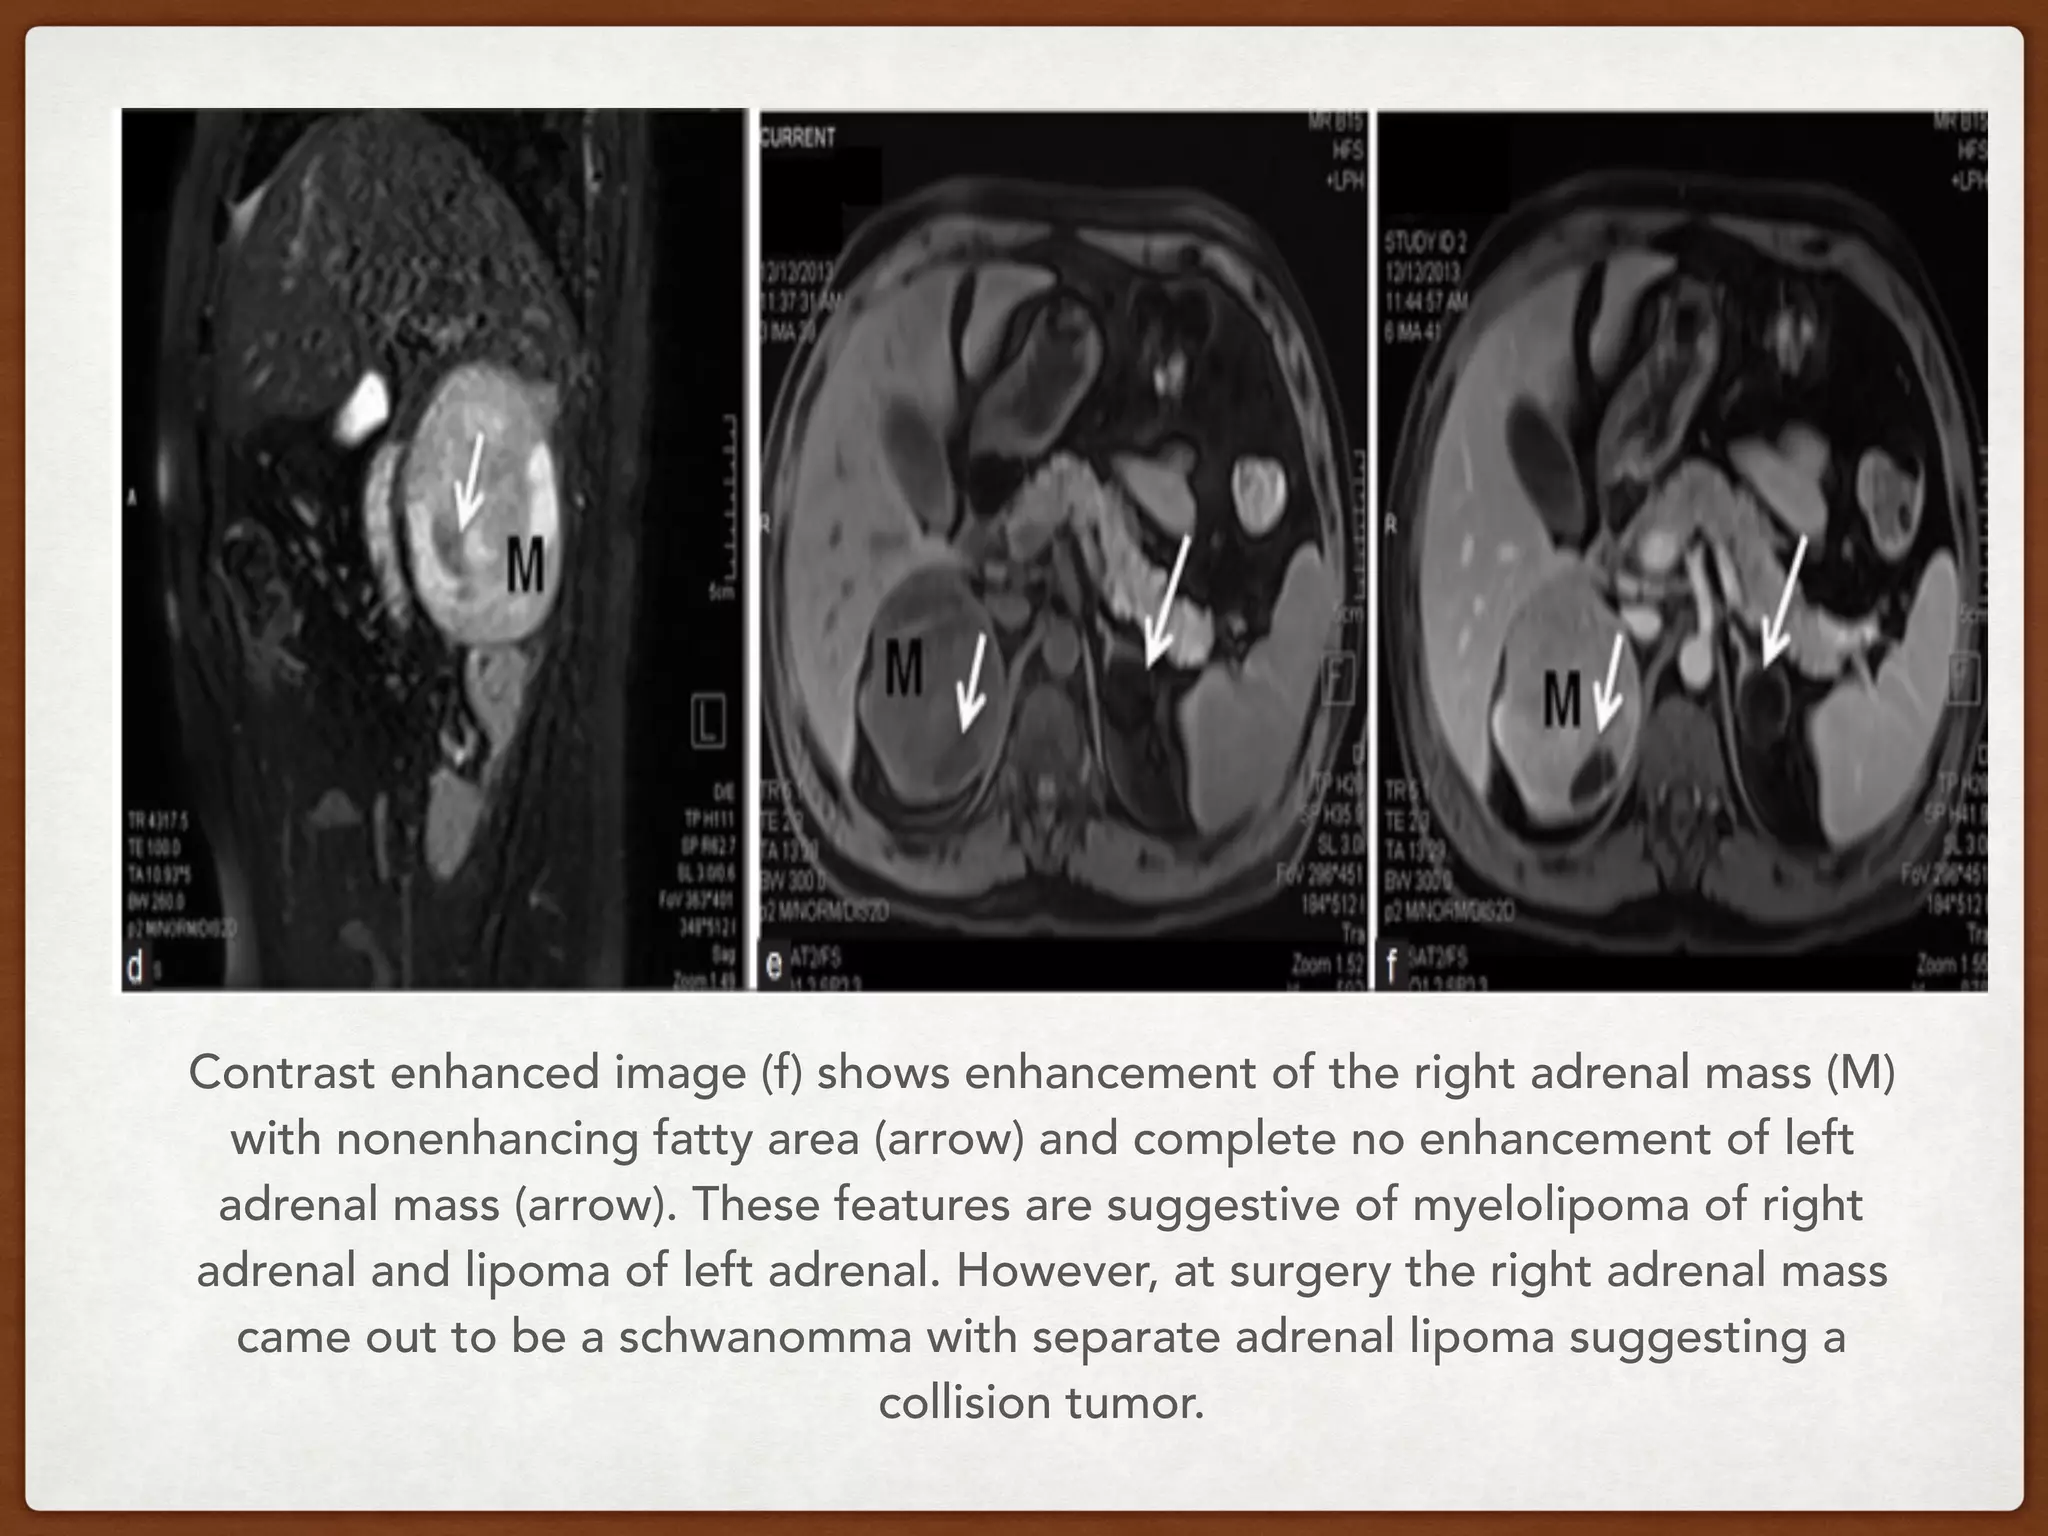

Figure 10: Collison tumor: Schwanomma with lipoma. T1 in-phase image (a)

showing a large hypointense right adrenal mass (M) and hyperintense left adrenal

mass (arrow). Out-of phase image (b) showing no signal drop of adrenal mass.

Coronal (c) and sagittal (d) fat saturated T2 weighted image show large

hyperintense right adrenal mass (M) with hypointense area (arrow) within likely to

represent fat. Fat saturated axial image (e) showing large mass (M) in the right

adrenal with area of fat (arrow) and another completely fatty mass in left adrenal

(arrow). Note complete suppression of left adrenal lesion in image (c).

Contrast enhanced image (f) shows enhancement of the right adrenal mass (M)

with nonenhancing fatty area (arrow) and complete no enhancement of left

adrenal mass (arrow). These features are suggestive of myelolipoma of right

adrenal and lipoma of left adrenal. However, at surgery the right adrenal mass

came out to be a schwanomma with separate adrenal lipoma suggesting a

collision tumor.

Figure 10: Collisontumor: Schwanomma with lipoma. T1 in-phase image (a) showing a large hypointense right adrenal mass (M) and hyperintense left adrenal mass (arrow). Out-of phase image (b) showing no signal drop of adrenal mass. Coronal (c) and sagittal (d) fat saturated T2 weighted image show large hyperintense right adrenal mass (M) with hypointense area (arrow) within likely to represent fat. Fat saturated axial image (e) showing large mass (M) in the right adrenal with area of fat (arrow) and another completely fatty mass in left adrenal (arrow). Note complete suppression of left adrenal lesion in image (c).

• 83.

Contrast enhanced image(f) shows enhancement of the right adrenal mass (M) with nonenhancing fatty area (arrow) and complete no enhancement of left adrenal mass (arrow). These features are suggestive of myelolipoma of right adrenal and lipoma of left adrenal. However, at surgery the right adrenal mass came out to be a schwanomma with separate adrenal lipoma suggesting a collision tumor.